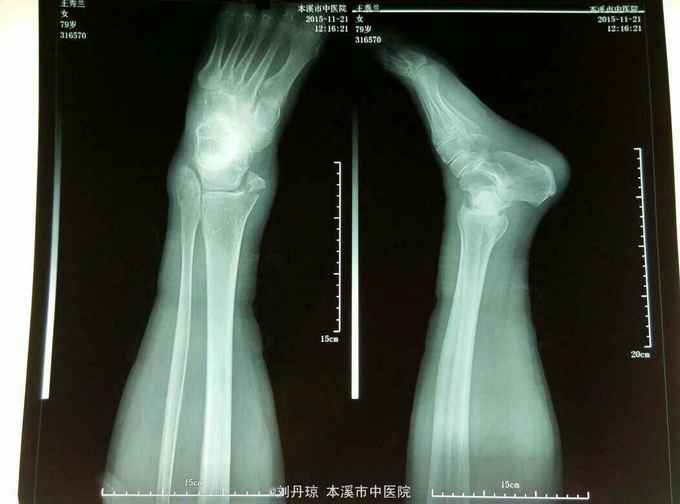

左踝关节刺痛,活动受限2小时。病史:患者2小时前下楼梯时不慎扭伤左踝,伤后左踝刺痛,活动受限,遂来我院门诊求治。既往:冠心病史20年,心梗病史1年。

左踝关节畸形,肿胀明显,压痛阳性,左踝关节功能障碍。足背动脉搏动清,足趾活动良好。辅查:DR:左踝关节骨折,三踝骨折移位明显。

诊断:左踝关节骨折 旋后外旋型IV度 治疗:手法整复,活血膏外用,夹板固定。接骨丹口服。